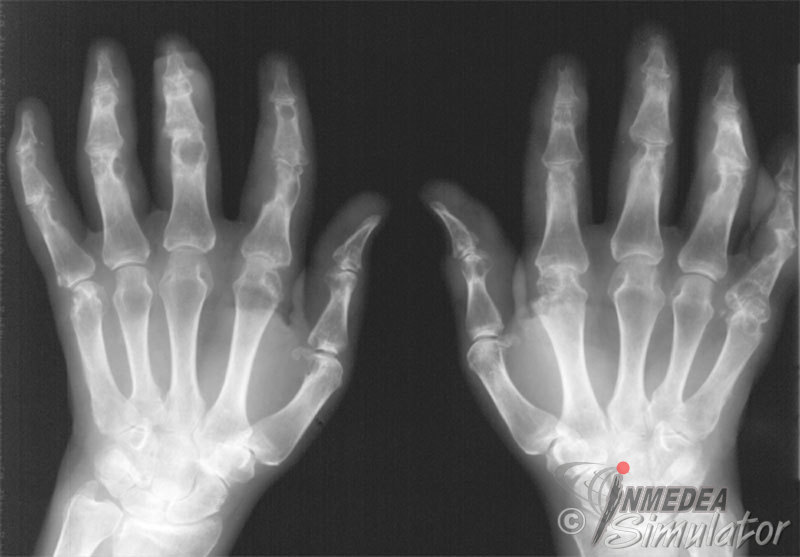

Arthritis Urica Definition. by mayo clinic staff. It's characterized by sudden, severe attacks of pain, swelling, redness. gout is a common and complex form of arthritis that can affect anyone. high uric acid levels can increase the risk of gout, which is a type of arthritis, and lead to other health problems. gout is a type of inflammatory arthritis that causes sudden, painful attacks of swelling, tenderness, and redness in one or more joints. low uric acid is defined as less than 2 mg/dl. A high uric acid level can be the result of the body making too much uric acid, not getting rid. Learn more about uric acid here. You’ve probably heard about high uric acid, or hyperuricemia,. gout is a type of arthritis that happens when you have too much uric acid in your blood and it forms sharp crystals. gout is a type of inflammatory arthritis caused by small crystals of a chemical called uric acid that form in the joints. gout is a type of arthritis caused by an excess of a chemical called uric acid, also called urate.

Arthritis Urica Definition by mayo clinic staff. gout is a type of inflammatory arthritis that causes sudden, painful attacks of swelling, tenderness, and redness in one or more joints. low uric acid is defined as less than 2 mg/dl. gout is a type of inflammatory arthritis caused by small crystals of a chemical called uric acid that form in the joints. high uric acid levels can increase the risk of gout, which is a type of arthritis, and lead to other health problems. gout is a common and complex form of arthritis that can affect anyone. A high uric acid level can be the result of the body making too much uric acid, not getting rid. You’ve probably heard about high uric acid, or hyperuricemia,. by mayo clinic staff. Learn more about uric acid here. It's characterized by sudden, severe attacks of pain, swelling, redness. gout is a type of arthritis caused by an excess of a chemical called uric acid, also called urate. gout is a type of arthritis that happens when you have too much uric acid in your blood and it forms sharp crystals.